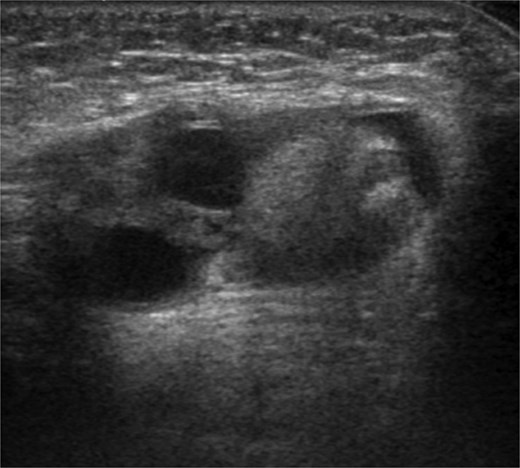

A 6-month-old female with low birth weight (birth weight: 436 g, gestation period: 28 weeks and 6 days) and a history of neonatal intensive care unit admission visited our department due to a left inguinal bulge. Her medical history included premature ductus arteriosus, for which she underwent ligation surgery 5 days after birth. She also required ventilatory support and administration of sildenafil citrate after birth due to persistent neonatal pulmonary hypertension. At the time of presentation to our department, the patient required home oxygen therapy (0.5 L/min). Abdominal ultrasonography revealed a hernia sac in the left inguinal region. A single circular, highly echogenic mass was observed within the sac, raising suspicion of herniation of the ipsilateral ovary (Fig. 1). Considering the risk of torsion and necrosis of the affected ovary, semi-urgent hernia repair (Potts’ procedure) was performed 6 days after the initial presentation. During the procedure, we identified two ovaries in a single hernia sac. One ovary, the left, had prolapsed into the hernia sac due to sliding, while the other was the right ovary (Fig. 2). The right ovary exhibited no adhesions to the surrounding tissue and was manually repositioned in the abdominal cavity. The left ovary was returned to the abdominal cavity by applying a purse-string suture to the hernia sac at the peripheral margin of the ovarian attachment. The postoperative course was uneventful, and the patient was discharged 7 days following surgery. No complications occurred. At 1-year follow-up, the patient remained recurrence-free.

Ultrasonography revealed a 12 mm-sized circular highly echogenic mass and 7- and 8-mm-sized cystic masses within the hernia sac. Ipsilateral ovarian herniation was suspected.